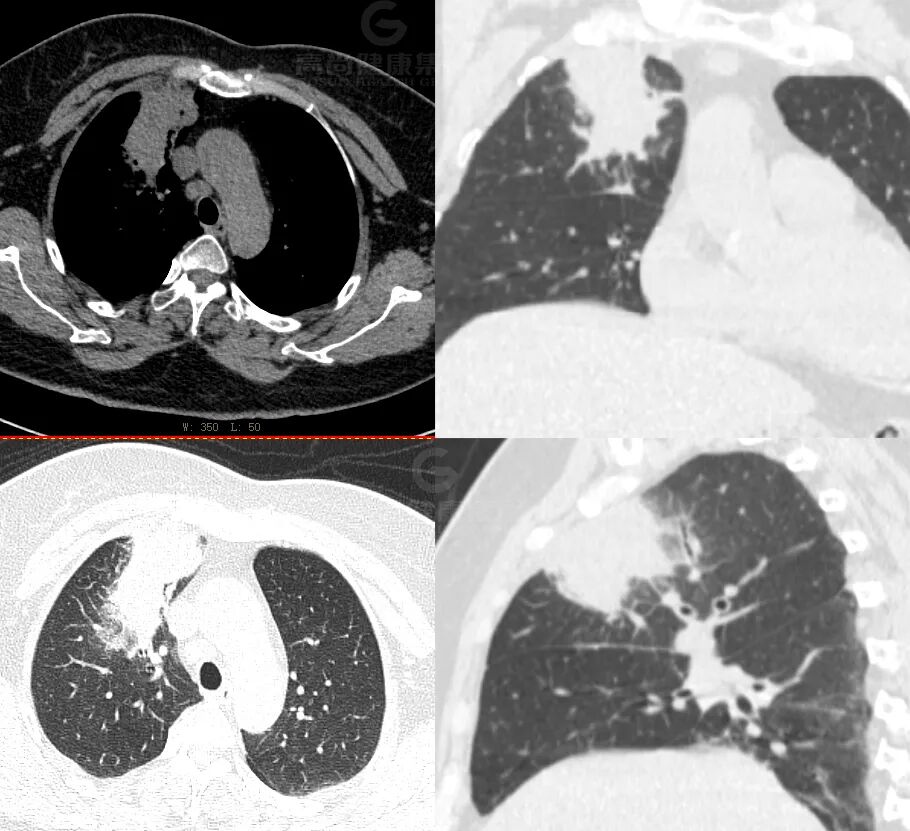

肺癌伴肺转移,周围出现「晕征」——肿瘤周围浸润及间质反应所致。

病例 5

描述

PET/CT 显像全身多发高代谢病变,左上肺癌伴肺、骨广泛转移。